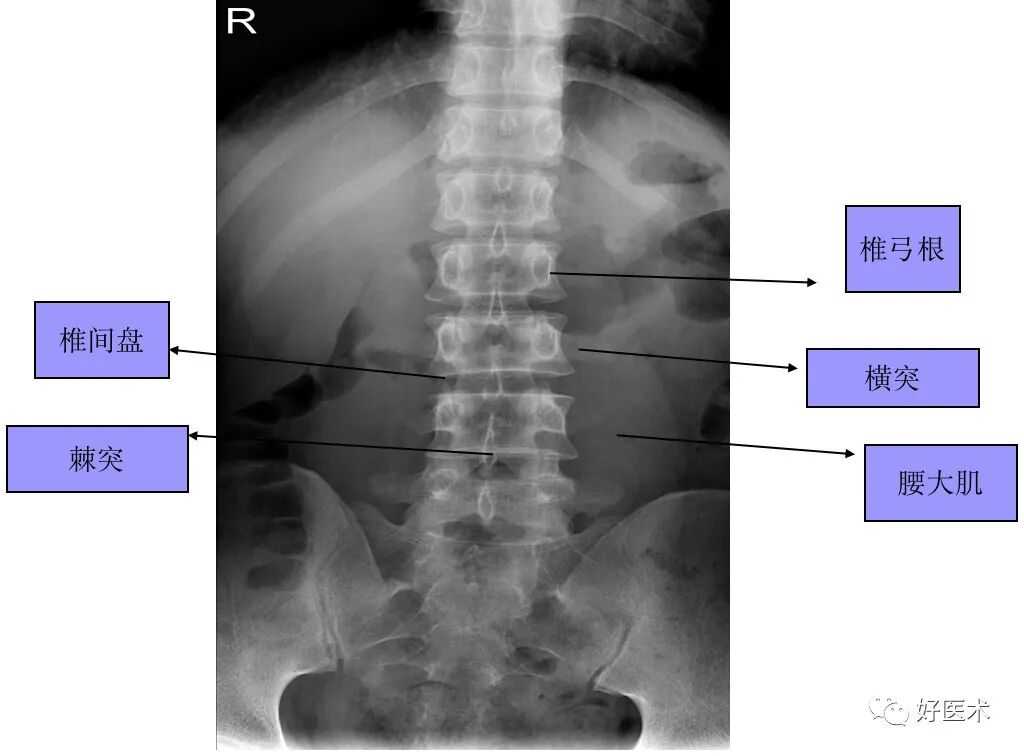

3. 腰椎

椎体:L1 ~L5 体积递增

椎弓根:比胸椎长和宽,椭圆形

棘突:水平,方形

横突:比胸椎小

椎间孔:大,但神经根受压风险增加

椎孔:大得能够容纳马尾和神经根

腰段椎管的形状:从上而下为卵圆形----三角形---三叶形